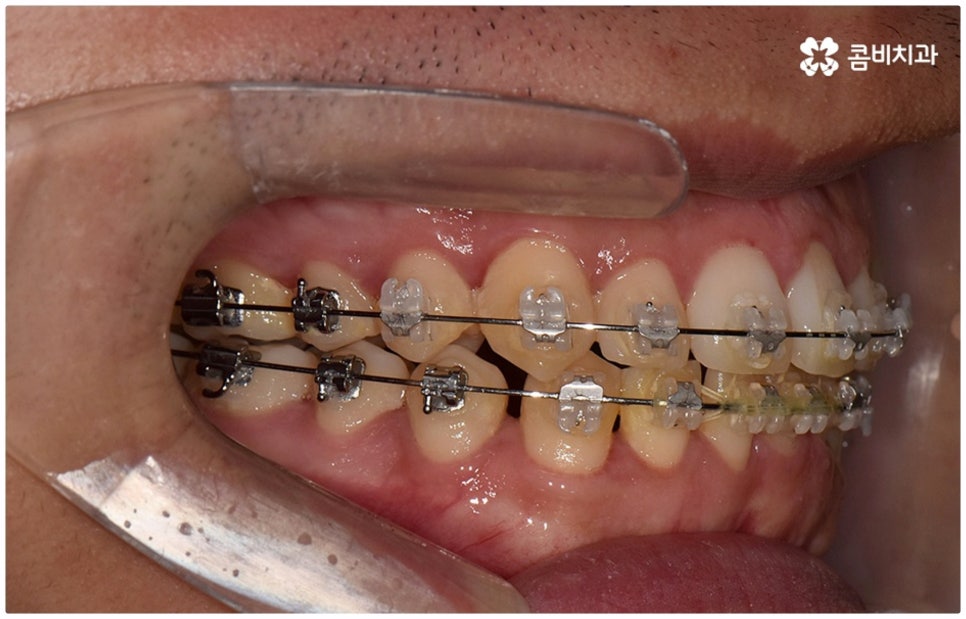

물론 교정 치료에 적기가 정해져 있는 것은 아니기 때문에 성인 이후 중장년 환자분들이라도 교정 치료가 불가능하지는 않으며 상황에 따라 비수술적인 방법으로도 얼마든지 불편함을 줄일 수 있는 경우가 있으니 정확하게 진단한 후 각자에게 맞는 교정 계획을 세워 무리하지 않게 치료를 진행하시길 바라고 있어요. 특히 턱관절과 관련된 부분을 개선하기 위해서는 양악 수술 밖에 방법이 없는 것이 아닌가 생각하셨던 분들이라면 먼저 치과에 내원하셔서 검진과 상담부터 진행해 보시면 마음의 부담을 덜 수 있어 좋을 거예요. 부정교합 3급 치열 (절단교합과 일부 반대교합이 병행되어 있음) 을 가지고 있는 성인분도 교정 치료를 통해 훨씬 자연스럽게 개선이 가능할 수 있으며, 관련 기술 개발 및 미니스크류 등 여러 장치의 발전을 통해 예전에는 적용이 어려웠던 케이스들도 이제는 교정 치료의 도움을 받을 수 있습니다.

위 사진은 이해를 돕기 위한 이미지이며, 환자의 동의하에 진행되었습니다.

전체 치료 기간은 약 18개월이 소요되었으며,

개인에 따라 출혈 및 부작용이 발생할 수 있고,

환자마다 치료 결과 및 기간이 상이할 수 있으므로,

정확한 치료 기간 및 치료 계획은

치과에서 상담을 받아보시길 권장 드립니다.